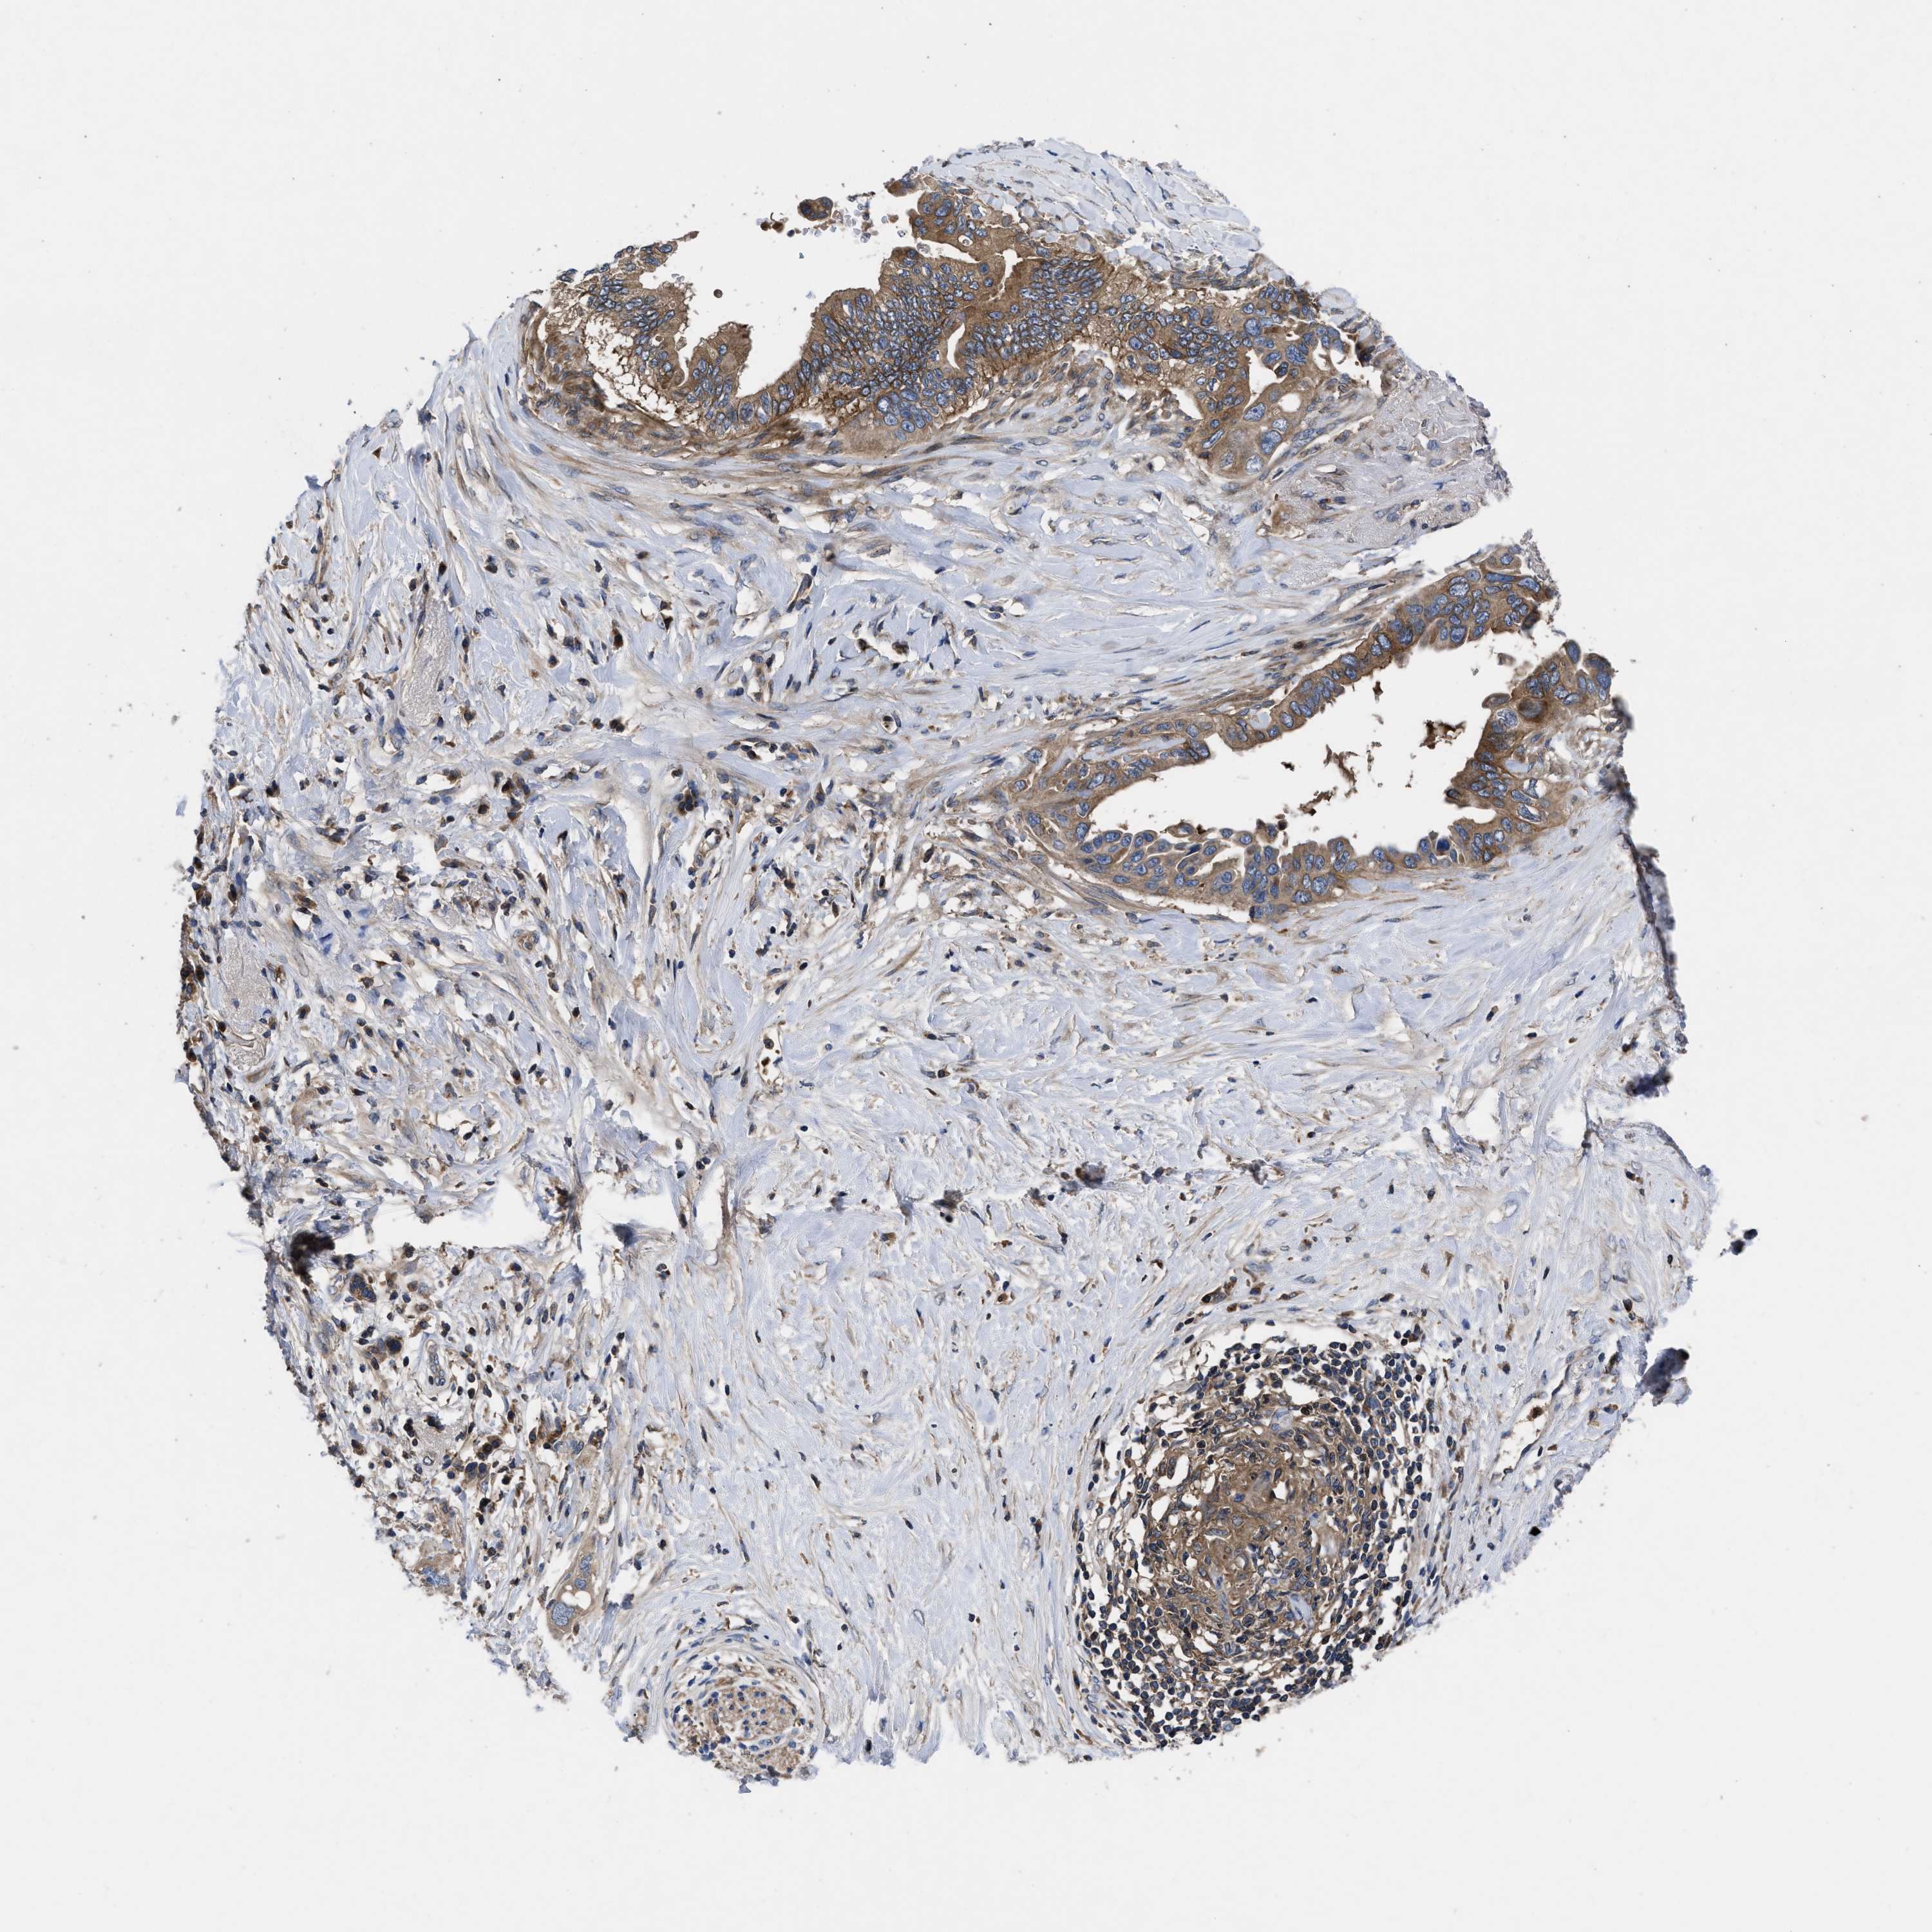

PANCREATIC CANCER - Protein expressioni

A mouse-over function shows sample information and annotation data. Click on an image to view it in a full screen mode. Samples can be filtered based on level of antibody staining by selecting one or several of the following categories: high, medium, low and not detected. The assay and annotation is described here.

Note that samples used for immunohistochemistry by the Human Protein Atlas do not correspond to samples in the TCGA dataset.

Antibody stainingi

Antibody staining in the annotated cell types in the current human tissue is reported as not detected, low, medium, or high, based on conventional immunohistochemistry profiling in selected tissues. This score is based on the combination of the staining intensity and fraction of stained cells.

Each image is clickable and will lead to virtual microscopy that enables deeper exploration of all samples and also displays staining intensity scores, fraction scores and subcellular localization as well as patient and tissue information for each sample.

Antibody HPA018162

Staining

High

Medium

Low

Not detected

Intensity

Strong

Moderate

Weak

Negative

Quantity

>75%

75%-25%

<25%

None

Location

Nuclear

Cytoplasmic/membranous

Cytoplasmic/membranous,nuclear

Adenocarcinoma, NOS